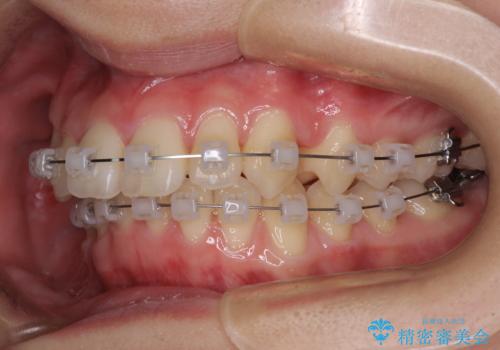

ぱっと見はインビザラインによる矯正治療も可能と思われましたが、歯根が最も長い犬歯がクロスバイトになっており、インビザラインでは対応困難と判断され、ワイヤー装置にて矯正治療を行うこととしました。

クロスバイトになっている犬歯は、歯の移動に伴い装置を張り替えていくことで対応することとしました。

クロスバイト改善中には歯髄壊死を起こすリスクがあるため、神経に問題がないか確認しながら治療を進めて行く必要があります。